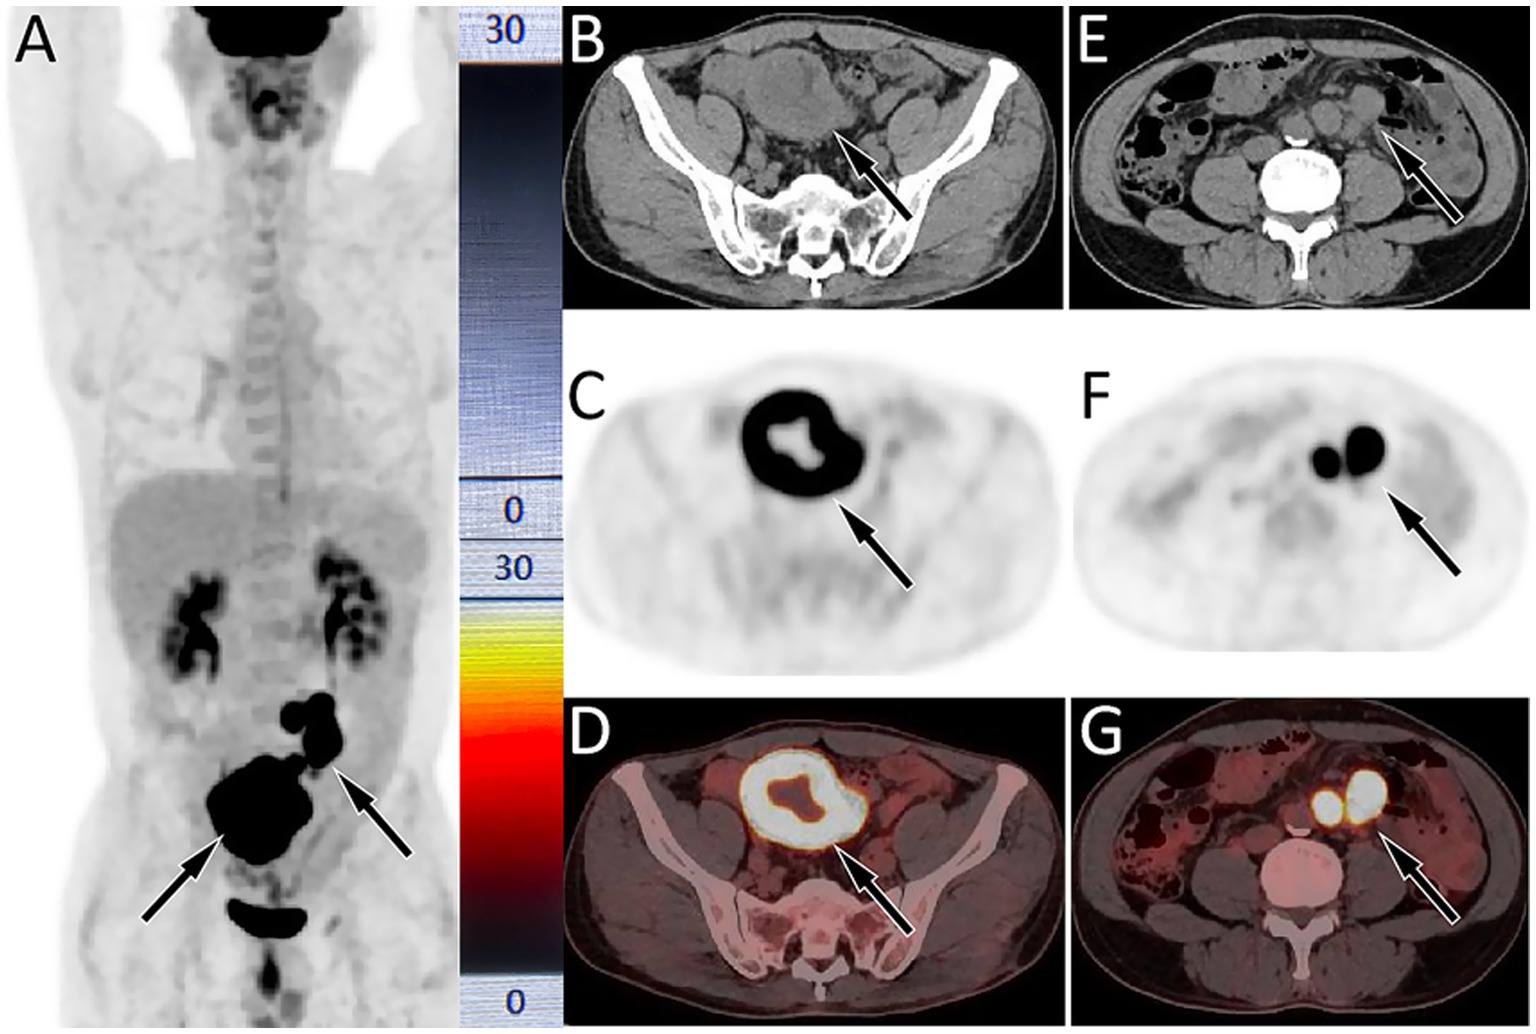

The patient subsequently underwent a puncture biopsy of the left pulmonary lesion and histopathology revealed sheets of large polygonal cells with abundant eosinophilic cytoplasm, prominent nucleoli, and frequent mitotic figures in the lesion. Immunohistochemistry showed diffuse positivity for CKpan, while Napsin A, CgA, CK56, CK5/6, and TTF1were negative, supporting the diagnosis of LCLC. Based on the aforementioned imaging and histopathological findings, the patient was diagnosed with LCLC, T4N2M1, stage IV. Due to the advanced stage of the disease, surgical resection of the tumor was not feasible for the patient. The patient began receiving the GCP chemotherapy regimen consisting of gemcitabine, cisplatin, and paclitaxel on September 10, 2020. During this period, the patient experienced Grade 1 myelosuppression and leukopenia, both of which improved following symptomatic treatment. After completing 8 courses of chemotherapy, the patient underwent a chest CT scan on April 18, 2021 and the results showed complete resolution of the lung mass and enlarged lymph nodes in the mediastinum and hilum, indicating significant clinical improvement. Following discharge, the patient underwent routine chest CT surveillance every 3–6 months, with no evidence of tumor recurrence observed up to November 2022. Due to intermittent pain in the upper abdomen for 1 month, the patient underwent a gastroscopy at a local hospital on June 19, 2023, and was diagnosed with chronic atrophic gastritis. Following symptomatic treatment, no significant improvement was observed. For further evaluation and management, the patient returned to our hospital on February 15, 2024. Physical examination showed tenderness in the right mid-lower abdomen without rebound tenderness. Tumor markers of the digestive system, including carcinoembryonic antigen, Ca199, Ca72-4, and alpha-fetoprotein, were all with normal limits. Abdominal CT revealed a mass in the small bowel near the ileocecal region with enlarged mesenteric lymph nodes. Our hospital’s radiologists initially considered the possibility of small bowel cancer with lymph node metastasis. PET/CT examination (Figure 2) revealed significantly increased 18F-FDG uptake in both the small bowel mass and the mesenteric lymph nodes, suggesting a high possibility of malignant pathology, such as lymphoma or metastasis from LCLC. Following the completion of routine examinations, the patient underwent laparoscopic exploration, tumor resection, and jejunostomy on February 27, 2024. Postoperative pathology (as shown in Figure 3) confirmed metastatic poorly differentiated cancer, consistent with the immunohistochemical profile of LCLC, demonstrating expression of CKpan, Brg1, INI-1, while negative expression of Napsin A, CgA, CK56, CK5/6, TTF1, etc. Following surgery, the patient resumed the GCP chemotherapy regimen. As of April 3, 2025, no significant evidence of tumor recurrence was observed during follow-up.

Figure 2. 18F-FDG PET/CT imaging (injected activity is 303.4 MBq) on February 21, 2024; The MIP (A) showed multiple significantly increased 18F-FDG uptake in the middle and lower abdomen (arrows). Axial CT (B) showed uneven annular thickening of the small bowel near the ileocecal region (arrow). The corresponding lesion had obviously increased 18F-FDG uptake on axial PET (C, arrow) and PET/CT fusion (D, arrow), with a maximum standardized uptake value (SUVmax) of 22.1. (E) Axial CT also showed multiple enlarged lymph node adjacent to the abdominal aorta (arrows); which were significantly increased 18FDG uptake on PET (F) and PET/CT (G), with a SUVmax of 21.6.